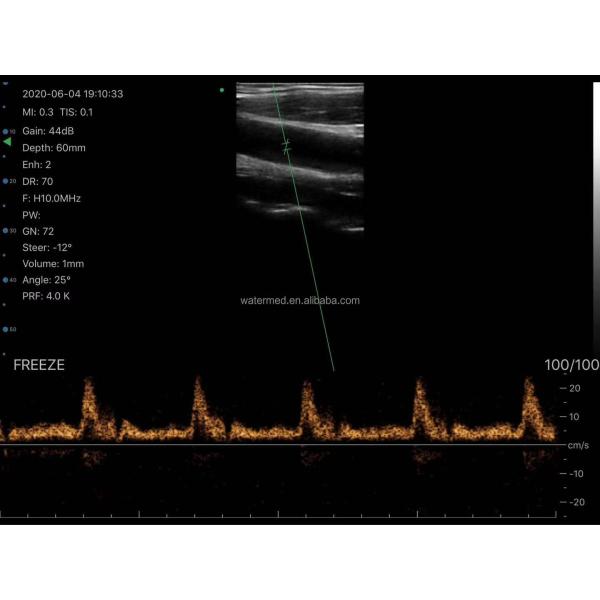

Linear/Convex/Phased Array 3 in 1 Handheld USB Ultrasound Double Probes Wireless Color Doppler Scanner Images |